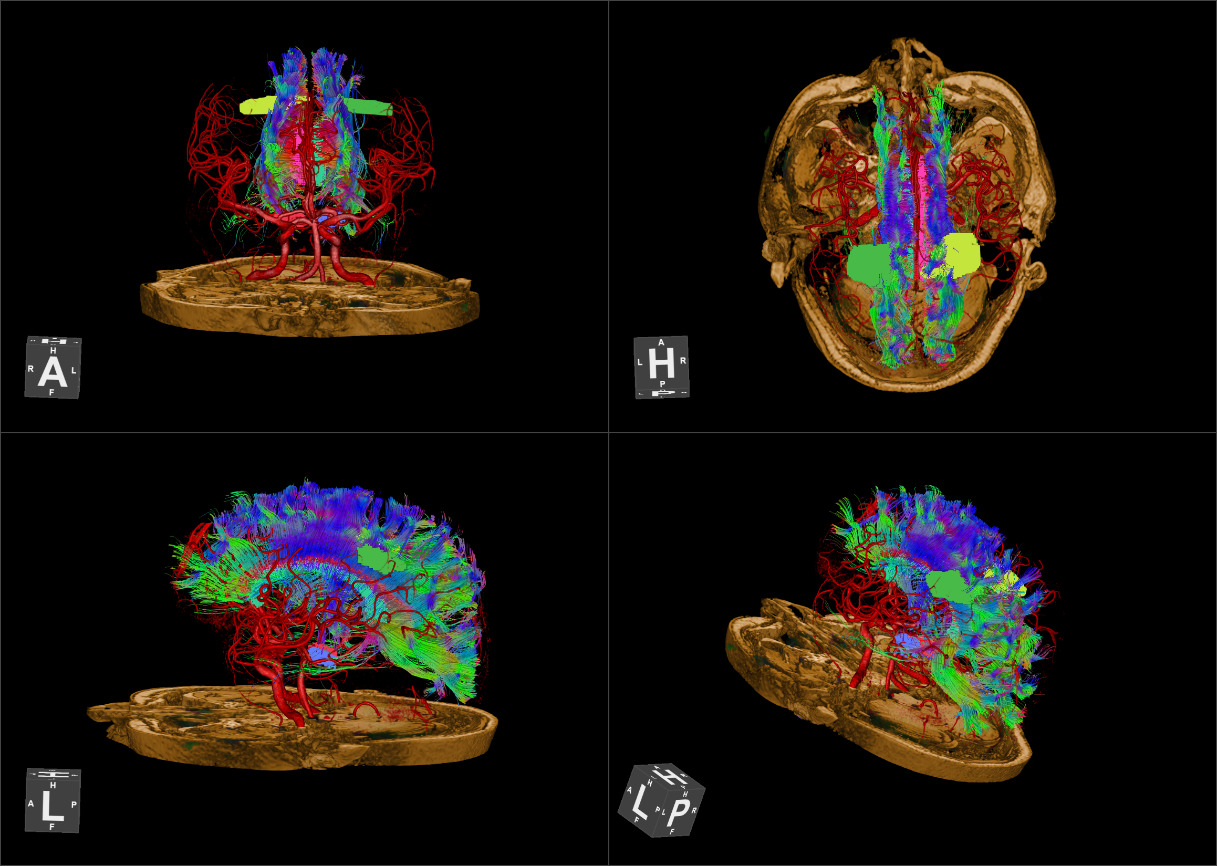

大脑结构 大脑血管及神经纤维束

脑膜瘤患者,手术前计划,通过高分辨脑表面血管与瘤体病变,脑整体结构融合,获得明确定位表征信息。 脑中线视神经乳头胶质瘤,高分辨脑神经系统3D FLAIR成像技术显示视神经乳头胶质瘤的空间三维特征,DTI及纤维示踪后处理技术显示与手术入路相关穹隆及视路神经纤维束走行及特征。